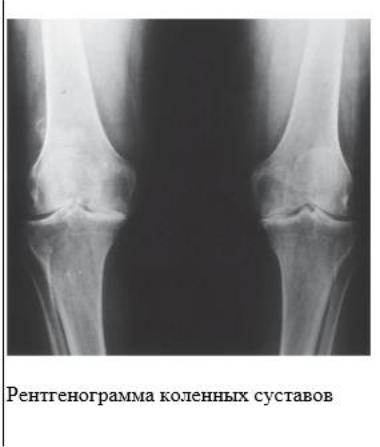

Больной М. 65 лет обратился в поликлинику с жалобами на одышку при небольшой физической нагрузке, периодически малопродуктивный кашель (особенно при переохлаждении, в сырую погоду), ощущение хрипов и тяжести в груди, сердцебиение.

Из анамнеза: курит 30 лет по пачке в день. Одышка появилась 3 года назад и стала прогрессировать за последний год. В течение последнего месяца, после перенесѐнного ОРЗ, одышка усилилась, мокроты стало выделяться больше, она приобрела жѐлто-зелѐный цвет. Несколько лет наблюдается с диагнозом «стенокардия II ФК», 2 года назад перенѐс крупноочаговый инфаркт миокарда переднебоковой, в связи с чем постоянно принимает Соталол, Кардиомагнил, Моночинкве (изосорбида-5-мононитрат).

Объективно: общее состояние средней тяжести. Лѐгкий акроцианоз. Больной пониженного питания, грудная клетка расширена в поперечнике, при перкуссии грудной клетки - лѐгочный звук с коробочным оттенком. При аускультации лѐгких - дыхание ослабленное, в нижних отделах лѐгких сухие низкотембровые и пневмосклеротические хрипы, выдох удлинѐн.

При осмотре ЧДД - 24 в минуту, ЧСС - 100 в минуту. АД - 130/80 мм рт. ст.

На ЭКГ: рубцовые изменения на боковой стенке левого желудочка. Единичные желудочковые экстрасистолы.

Спирография: ЖЕЛ - 52%, ОФВ1 - 37%, Тест Тифно - 57,2.

На рентгенограмме органов грудной клетки - признаки эмфиземы и пневмосклероза лѐгких.

Общий анализ мокроты: лейкоциты – до закрытия полей зрения, нейтрофилы - 90%, лимфоциты - 10%.